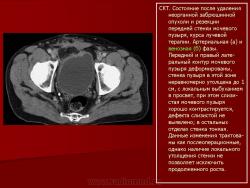

Онкология. Фибросаркома забрюшинного пространства. +

Фибросаркома забрюшинного пространства.